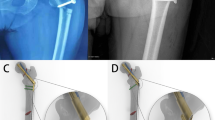

Three geometric models of the necrotic femur after multiple drilling operations were fabricated through Boolean operations as virtual surgical operations (Fig. 1c).26 An entry hole in the subtrochanteric region of the femur was defined as an overlapped hole of two drillings of 3.2 mm diameter in different directions toward the necrotic region. Therefore, models fabricated with 3, 5, and 7 entry holes in the subtrochanteric region contained 6, 10, and 14 drilling channels, respectively.

Two geometric models of short hole distance and changed entry hole position with 7 entry holes and 14 drilling channels were fabricated. In the short hole distance model, the distance between holes was decreased to half the hole radius. In the changed hole position model, all holes were assumed to be drilled in the subtrochanteric region close to the posterior region (Fig. 1d).

To evaluate the effects of drilling numbers on femoral failure, the von Mises stress, principal stress, and principal strain of the femur were calculated and compared with the yield stress, tensile strength, and yield strain of the femur, respectively. Figure 4a shows the von Mises stress distributions of the intact femur model and the model with 14 drilled channels in the subtrochanteric region. The stress distribution of the subtrochanteric region close to the posterior region of the femur in the intact femur model was higher than that of the other region. In the 14 channel model, we found increased stress around the entry holes compared with the stress distribution in the intact femur model. The highest stress concentration was found around the entry hole at the subtrochanteric region close to the posterior region. In Fig. 4b, the principal strain distributions in the intact femur model and the 14 channel drilling model were compared. The 14 drilling model showed increased principal strain distributions, with the highest strain concentration found around the entry hole in the same region having the highest concentration of von Mises stress.

To evaluate the effects of entry hole location, two models of short hole distance and changed entry hole position with 7 entry holes and 14 drillings were used for calculation of the von Mises stresses in the femur (Fig. 4c. We found that the models did not show a broad region of concentrated stresses. The calculated peak values of von Mises stress in the two models were 33.13 and 27.03 MPa, respectively, and did not show a notable increase in peak values compared to those of the multiple drilling model prior to changing the entry hole location.